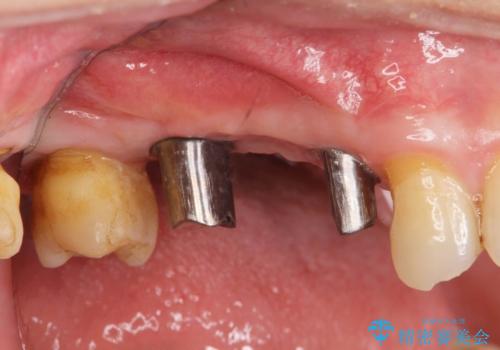

- 右上の奥歯を失ってしまい、「全然モノが噛めない、しっかりと噛めるようになりたい。」

、と入れ歯ではなくインプラント治療を希望され来院されました。

3本の歯が失われた状態を、2本のインプラントで支えるブリッジでの咬合機能回復を計画します。